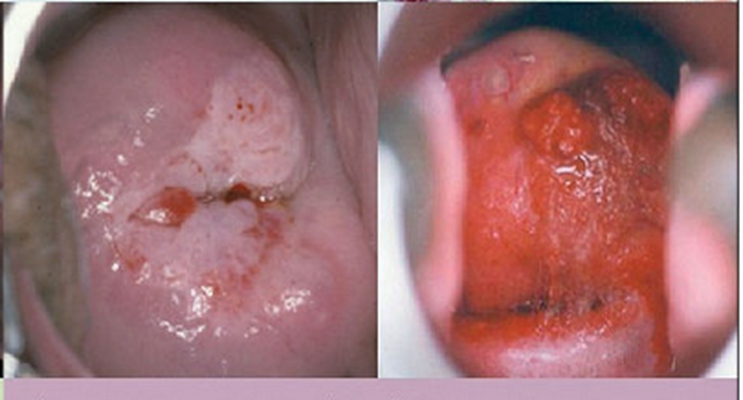

子宮頸癌前病變圖片

宮頸癌的早期症狀

宮頸癌的早期症狀

宮頸癌的早期症狀

宮頸癌的早期症狀

宮頸癌的早期症狀

宮頸癌的早期症狀

宮頸癌的早期症狀

宮頸癌的早期症狀

宮頸癌的早期症狀

宮頸癌的早期症狀